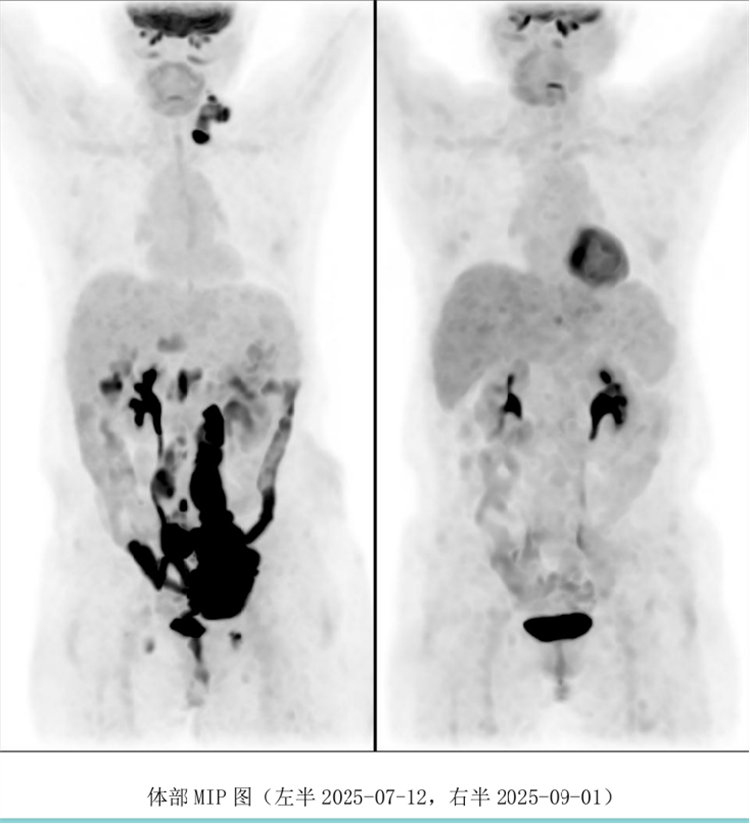

病例匯報環(huán)節(jié)由我院淋巴瘤科張薇醫(yī)生帶來了三例精彩紛呈的難治復(fù)發(fā)彌漫大B淋巴瘤CAR-T治療的病例。

病例過程跌宕起伏,從橋接治療到靶點的選擇,并發(fā)癥的處理都極具代表性。張醫(yī)生詳盡分享了患者在治療過程中的挑戰(zhàn)、決策依據(jù)以及CAR-T細(xì)胞治療后的驚人緩解與轉(zhuǎn)歸,充分展示了CAR-T技術(shù)為晚期患者帶來的突破性生存希望。